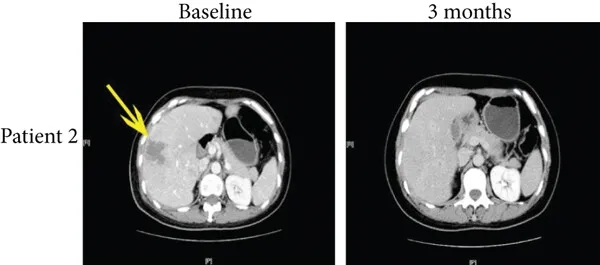

尤为值得关注的是,两例完全缓解患者的疗效更为亮眼:

病例2是一位50岁患者,治疗前伴肝转移,患者在接受免疫治疗4个月后,多发性肝转移达到完全缓解(详见下图b,黄色箭头所示),PFS达10.9个月。

▲图源“J Immunol Res”,版权归原作者所有,如无意中侵犯了知识产权,请联系我们删除